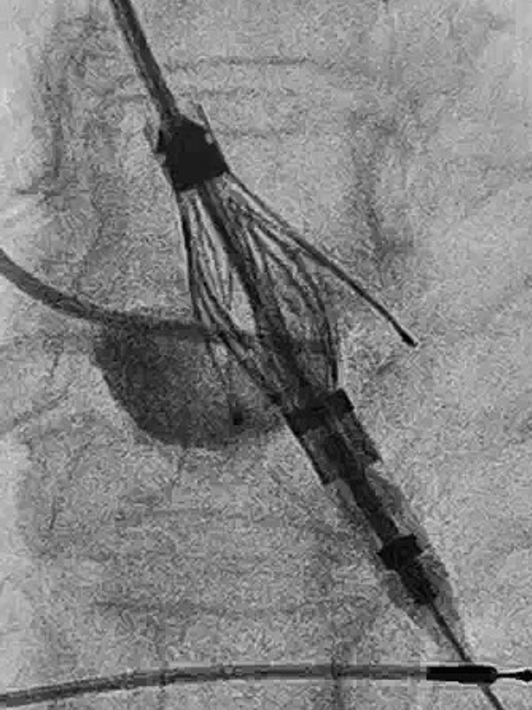

患者全麻后植入Safari预塑弯导丝,猪尾根部造影后,置换MP导管,使用TaurusTrio THV27进行植入,首先将TaurusTrio 导引鞘推进到STJ上方。输送系统装载27规格瓣膜,到达STJ上初始释放位,回撤长鞘到降主动脉位置。使用调弯功能调整轴向,推进1cm展开定位键后,调整DSA验证定位键位置,可进行整体旋转瓣膜进行瓣窦对齐,确保在coplanar View三个定位键与原生窦对齐,推进瓣膜使定位键进入窦底,逐一造影验证后,在起搏下释放。完成植入后造影结果显示重度主动脉反流消失,无瓣周漏,瓣膜释放形态较理想,且释放后无新发起搏器植入指征,顺利结束手术。

▲无冠窦造影定位

▲右冠窦造影定位

▲左冠窦造影定位